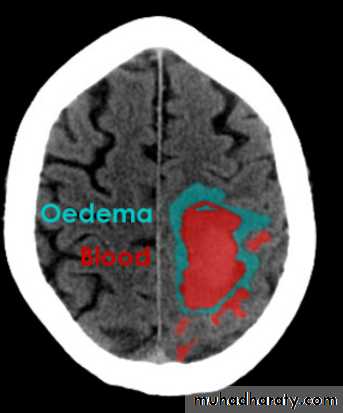

Acute Intra cerebral hematoma

CT finding :Hyper dense area , surrounded by edema , any where within the brain parenchyma.

Shifting of the midline

Compression of the ipsi lateral ventricle .

Associated with infarction , # , trauma concussion , tumor …..